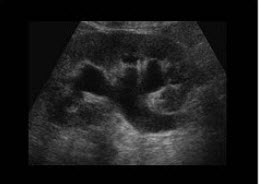

63、单项选择题

患者,女性,转移性右下腹疼痛4小时,超声见一长条低回光团,边界不清,如图所示,考虑为()

A.肝管结石

B.胆囊炎

C.附件炎

D.阑尾炎

E.肠梗阻